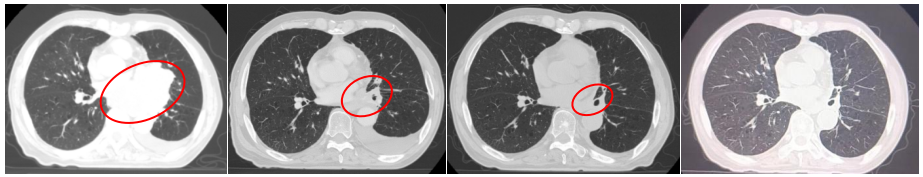

胸部增强CT(2022-05-23):1、左肺门占位(较大截面约7.8cm×8.3cm)伴纵隔多发肿大淋巴结、远端阻塞性肺炎、考虑中央型肺癌,累及左肺动脉及左心房、心室不除外。2、双肺肺气肿。3、左侧胸腔积液,累及左侧胸膜可能。4、心包少量积液。5、肝内多发小囊肿可能。

2022-07-19(2周期后)胸部、全腹部增强CT:1.肺癌复查,较前(2022-05-23)左肺门占位明显减小,左肺下叶远端阻塞性改变较前范围减小;2.双肺肺气肿;3.左侧胸腔积液,累及左侧胸膜可能,较前略增多;4.心包少量积液,较前增多;5.肝内多发囊肿;右肾上极小囊肿;6.肝左叶内小海绵状血管瘤可能;7.前列腺增大伴钙化。